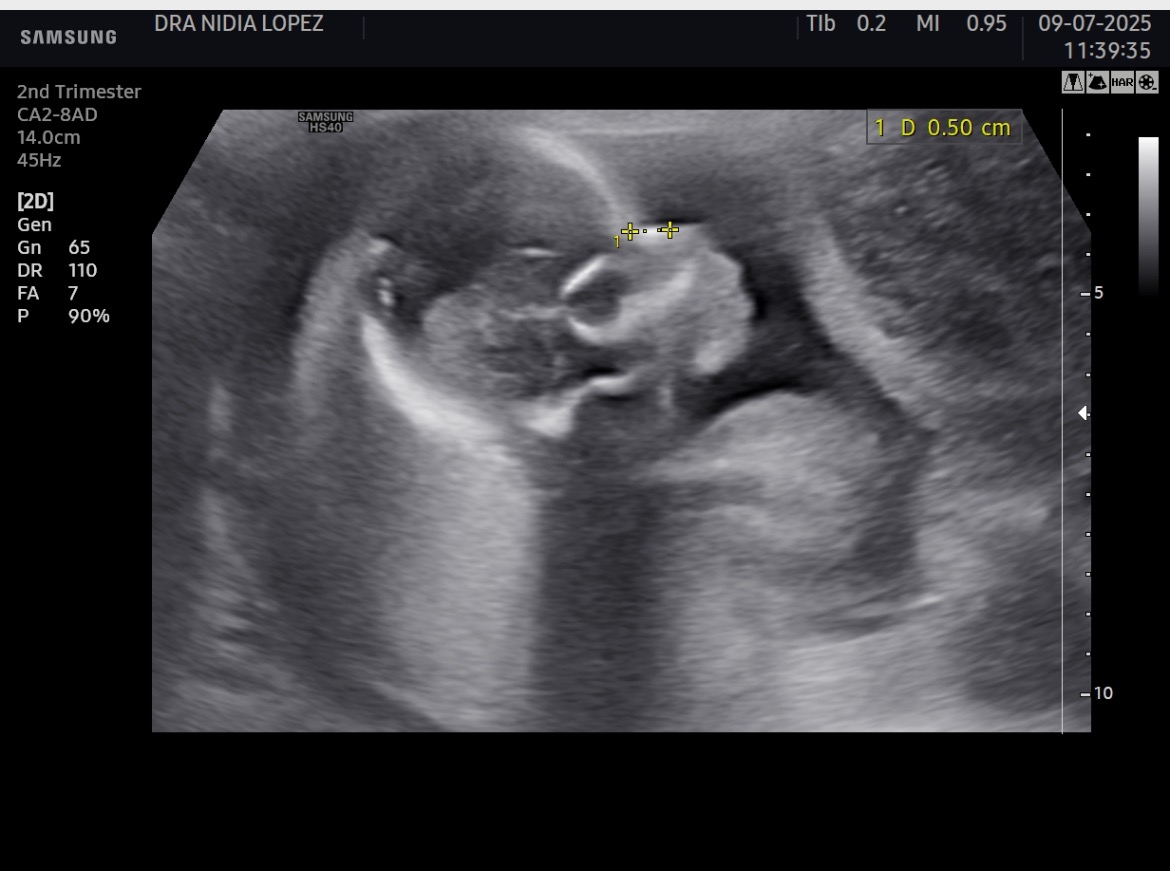

I lived in US all my life, after 30yrs I was sent to a country I knew nothing of where medical insurance is not provided which puts many of us at risk. I’m currently pregnant, which those who know me know I was NEVER able to another kid, 23yrs later I have a new baby, she’s a TRUE BLESSING and definitely a MIRACLE yet the pregnancy has had a lot of negative loopholes as I am extremely high risk. Im grateful we’ve gotten this far yet the father of the baby doesn’t seem to care much about the financial burden . He became very abusive to the point were the week after our first ultrasound he physically hurt me in a brutal way. I had to let go if I wanted my baby girl to survive. It breaks my sole as it has many single mothers to know we have to do this alone. If all goes well with my pregnancy my girl will be born next month yet I don’t have the funds to birth her in a hospital were they treat extreme high risk pregnancies. I want my baby. I never been the type to ask for help, yet here I am, I need help. Anything will be appreciated with all the strength left in me.